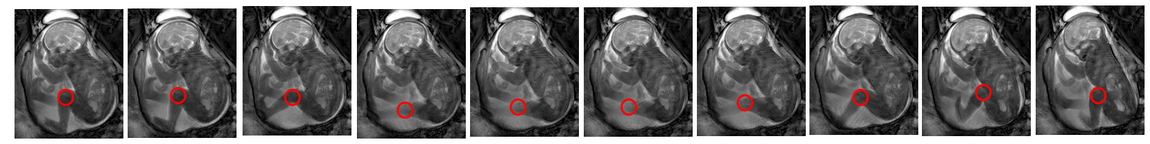

The Developmental Biomechanics Lab is seeking exceptional PhD studentship candidates to put forward for a competitive departmental studentship round. The project involves computational modelling of fetal movement, and is suitable to a candidate with Biomechanics and computational modelling skills. Suitable candidates should have an excellent track record, such as first class degrees, academic awards and/or extensive prior research experience. Prior publications are also an advantage. Funding restrictions mean that '''only candidates with UK nationality are eligible'''. To express interest, please email Dr Nowlan to describe how your interests and experience align with the project, and include your CV.

Fetal Movement Image